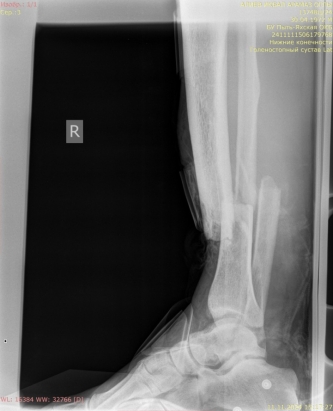

2) Мужчина, 57 лет. В результате падения бревна на область голени получил травму — открытый оскольчатый перелом верхней трети диафиза правой большеберцовой кости со смещением отломков (рис. 4).

Рис. 4.